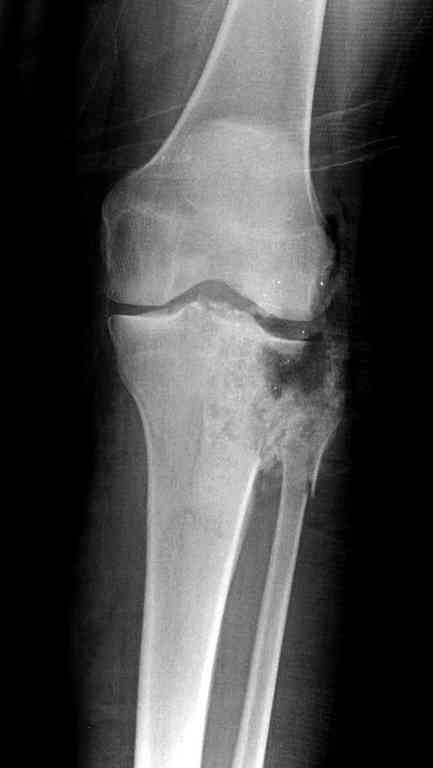

Одинокий кортикальный шуруп не удержит тибиальный бугор, сустав тибиал плато оставлен без репозиции и фиксации.

План с протезированием чересчур агрессивный, больная слишком молодая. В данный момент для удержания конструкции необходимо установить наружный фиксатор между бедром и голенью. Обработку продолжать с применением антибиотиков и вакуумирования.

Здесь применение материала Plexur http://www.plexur.com для пластики при дефектах кости у больной с огнестрельной раной латерального тибиал плато с повреждением малоберцового нерва. Несмотря на интактный медиальный мышелок, для профилактики от вальгуса установлен АВФ и сделана ангиограмма.